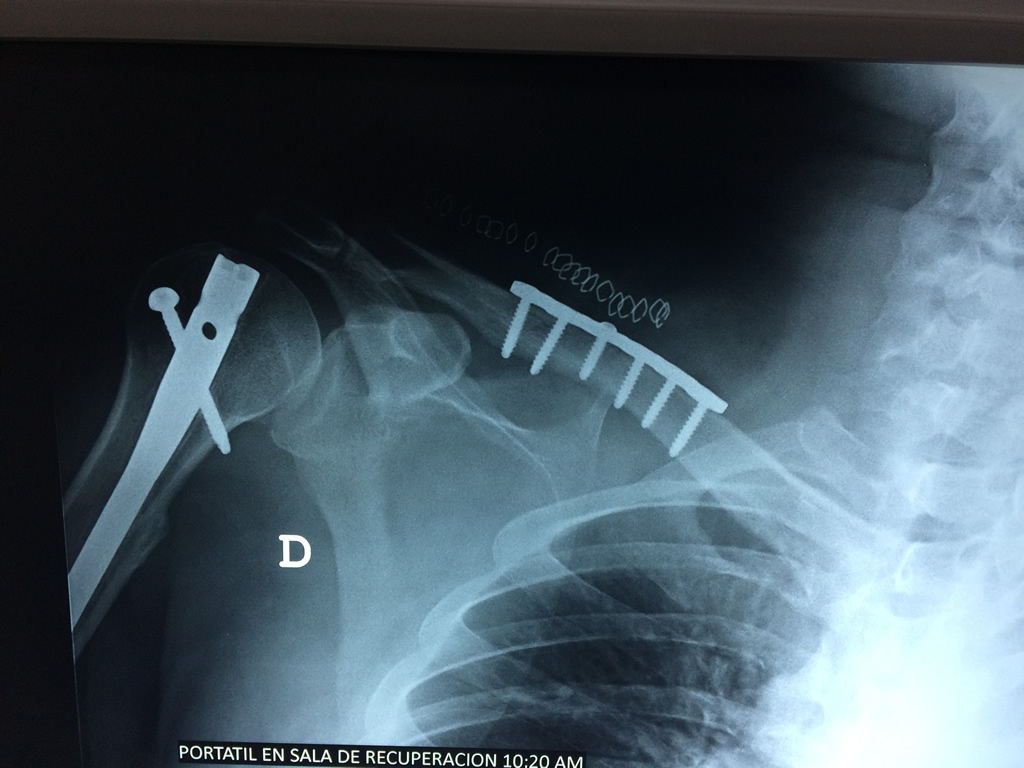

Cirugías de Hombros - Clavícula

La clavícula es un hueso largo, con forma de "S" itálica, situado en la parte anterosuperior del tórax. Junto con la escápula forman la cintura escapular. Se puede palpar por toda su longitud y se extiende del esternón al acromion de la escápula, siguiendo una dirección oblicua lateral y posterior.

Se considera el único medio de unión entre el miembro superior y el tórax. A pesar de su aspecto, similar al de un hueso largo, posee una estructura semejante a la de un hueso plano, ya que carece de epífisis y de diáfisis, lo que la harían entrar dentro de la clasificación de hueso largo. Carece de un canal medular propiamente dicho.